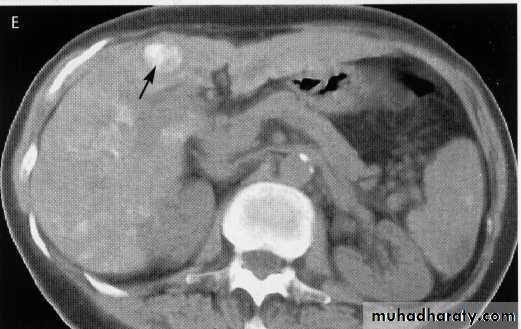

hepatic mets

hepatic mets,arterial phase